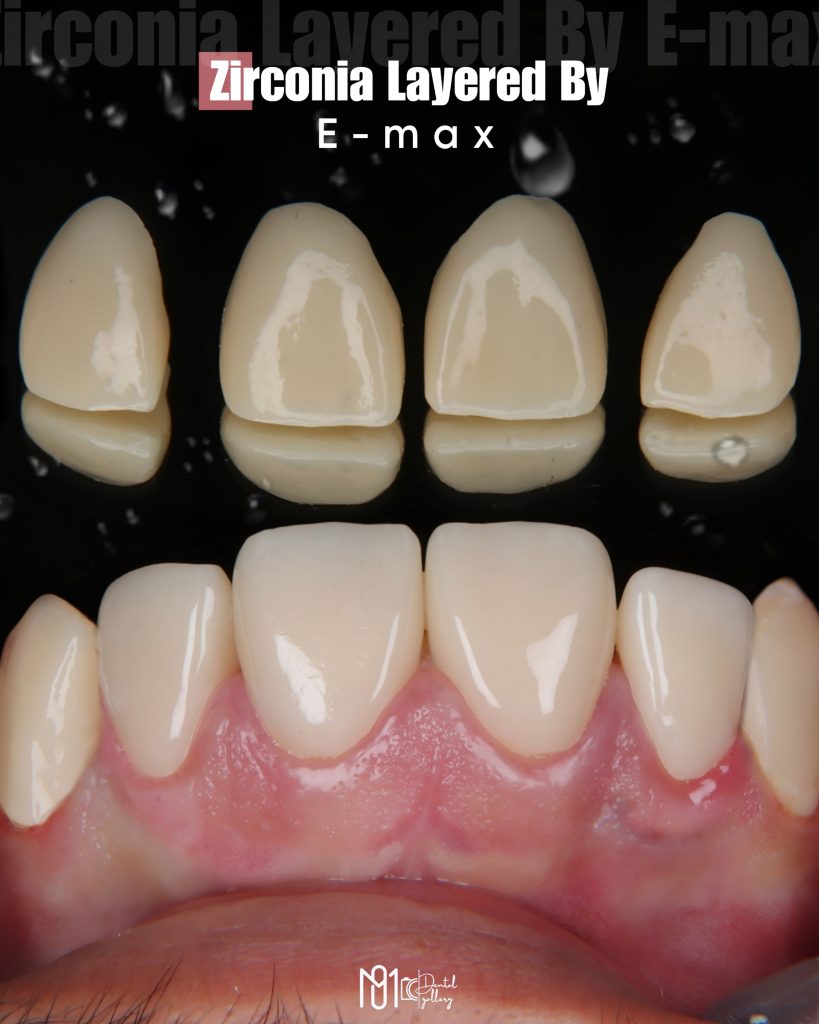

The case involved managing extensive carious lesions across both arches, performing root canal treatments, direct and indirect restorations, and even a periodontal surgical procedure.

I treated multiple deep caries cases using Immediate Dentin Sealing (IDS), performed Composite Resin Restorations (CRR) for both anterior and posterior teeth, and placed temporary restorations to maintain occlusion before the final prostheses.

In total, this case included 23 composite restorations, 7 full coverage crowns, and 2 root canal treatments, all completed between February 10th, 2025 and May 12th, 2025.